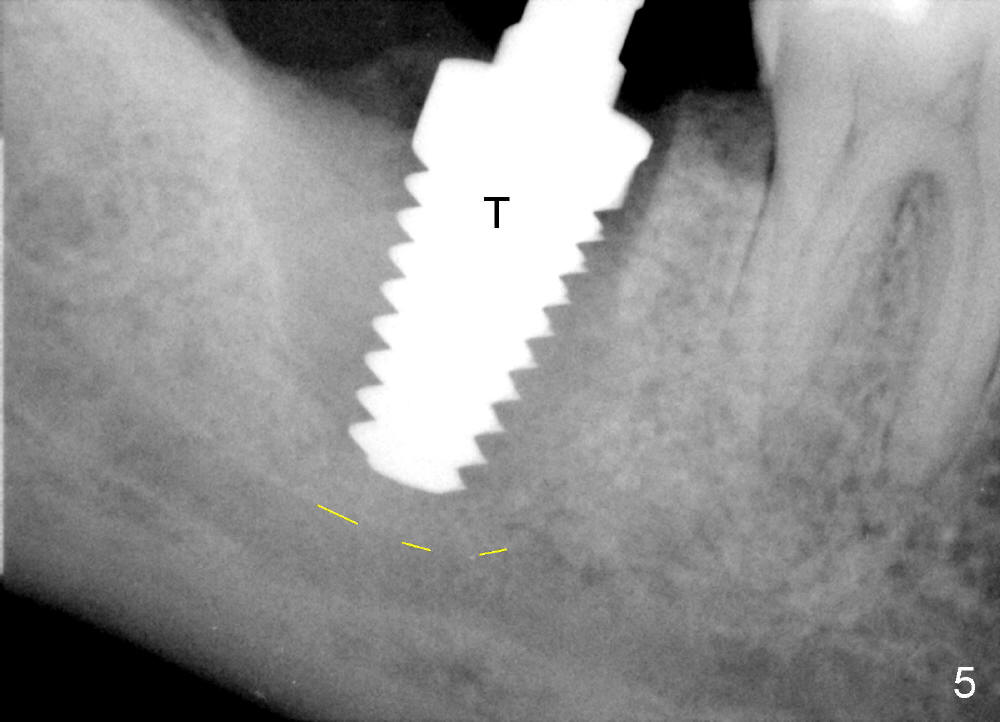

The tooth #31 of a 38-year-old lady has endo perio disease (Fig.1). Due to the large periapical lesion, there will be no solid (new) bone available for primary stability of an immediate implant (Fig.2: 7x17 mm). Yellow dashed line represents the upper border of the Inferior Alveolar Canal (IAC). Infiltration anesthesia is administered first. The mesiodistal widths of the root of the extracted tooth are 10 and 7 mm at the coronal and apical ends, respectively; the buccolingual ones 7 and 5 mm; the length 17 mm (Fig.3). The socket appears much larger than the root (Fig.4). To prevent paresthesia, no drills are used. Instead, a series of tap drills (6,7,8x17 mm) are sequentially inserted into the socket. The largest tap (Fig.5 T; 8x17 mm) binds to the socket securely with separation from IAC. Block anesthesia has to be administered before removal of the tap. A tapered implant (8x17 mm) is placed with insertion torque greater than 60 Ncm (Fig.6 I); allograft mixed with Osteogen is placed around the implant (*). Collagen dressing covers the opening of the remaining socket. The wound is protected with perio dressing, which is partially secured by an abutment (A in Fig.6). No paresthesia is reported by the patient a few hours postop.